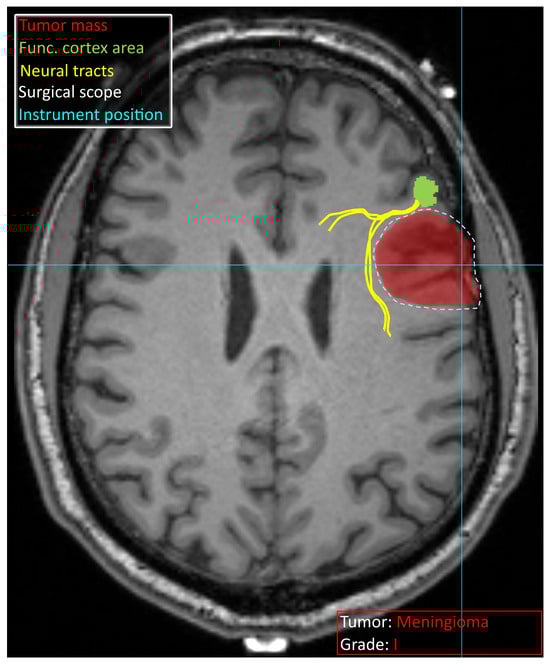

2.2. Decision Support in Preoperative Planning

2.3.1. Intraoperative Neuronavigation

- Mazzucchi, E.; La Rocca, G.; Hiepe, P.; Pignotti, F.; Galieri, G.; Policicchio, D.; Boccaletti, R.; Rinaldi, P.; Gaudino, S.; Ius, T.; et al. Intraoperative Integration of Multimodal Imaging to Improve Neuronavigation: A Technical Note. World Neurosurg. 2022, 164, 330–340. [Google Scholar] [CrossRef]

| Mazzucchi et al. [77] | Multimodal imaging for improving intraoperative neuronavigation | Fusion of T1w, T2w, DTI, Flair and ultrasound | MRI: T1w, T2w, DTI and Flair modalities; intraoperative ultrasound | Descriptive | Proprietary |

| Guo et al. [78] | Intraoperative MRI and ultrasound in diffuse glioma surgery | Fusion of T1w, T2w, DTI, DWI and ultrasound | MRI: T1w, T2w, DTI and DWI modalities; intraoperative ultrasound | Increased extent of resection, more cases with a total resection; increased operative time | Proprietary |

| Wei et al. [79] | Intraoperative MRI navigation for glioma resection | Segmentation dictionary learning algorithm | MRI: T1, T2, Flair, DTI and BOLD modalities | Descriptive | Proprietary |